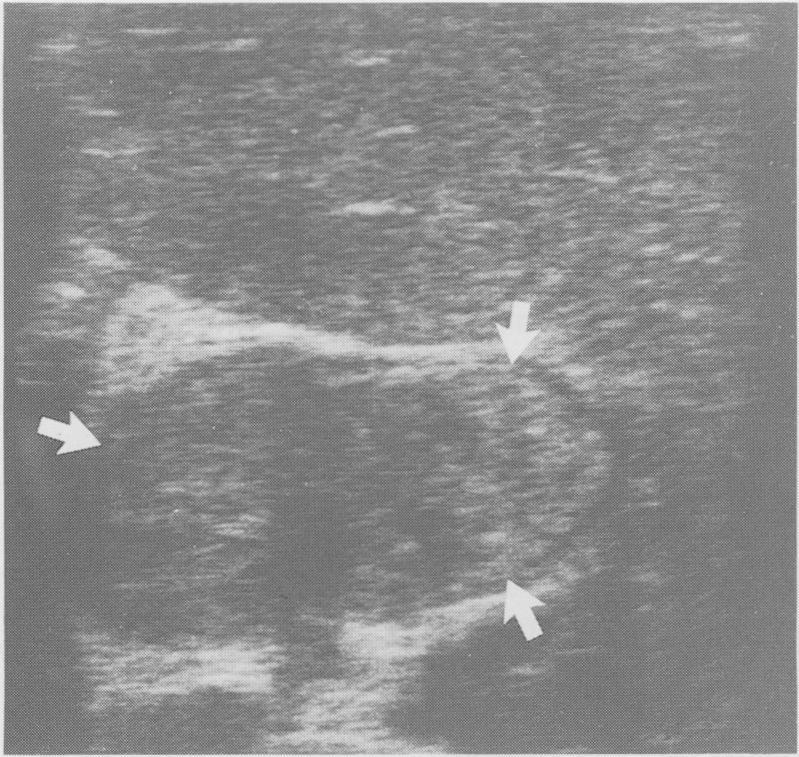

A case of villous adenoma of the common hepatic duct causing obstructive jaundice, where the diagnosis was made by ultrasound guided percutaneous biopsy is reported. At surgery ultrasonography was used to define the extent and operability of the tumour.

报告了一例肝总管绒毛状腺瘤导致梗阻性黄疸的病例,该病例通过超声引导下经皮活检作出诊断。手术时,超声检查用于确定肿瘤的范围和可切除性。